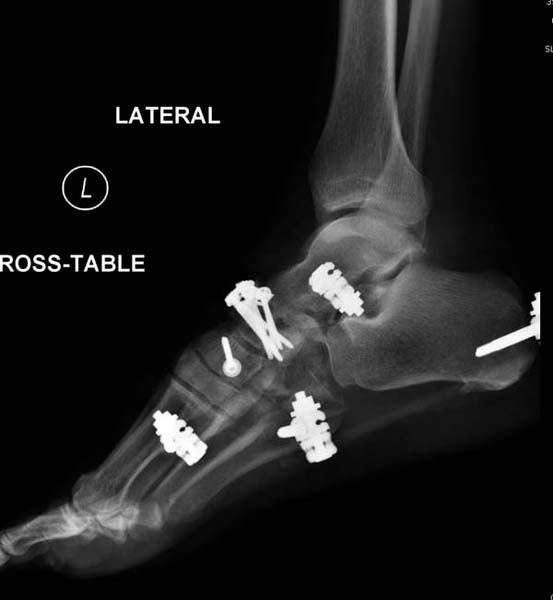

После спадения отека вариантов фиксации много, включая мининвазивную технику, но данный случай закончили установкой простого аппарата Илизарова.

Через три дня оперирована стопа и для нейтрализации сил колонн оставили наружный фиксатор.